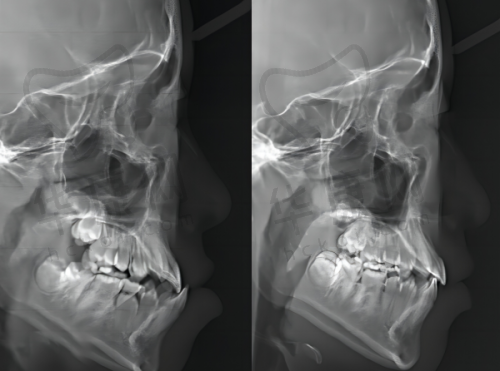

乌鲁木齐福宏林口腔医院以种植牙与正畸技术为核心竞争力,尤其在复杂病例处理上表现突出。在种植牙方面,采用All - on - 4即刻负重技术,结合3D导航可视化系统,能实现“半口修复仅需4颗植体”的方案,大大缩短了治疗周期。牙齿矫正方面,提供隐适美、时代天使等隐形矫正技术,兼顾了美观与舒适度。此外,医院还拥有口腔扫描仪、X光诊断系统等数字化设备,可精细获取患者数据,辅助制定个性化方案。